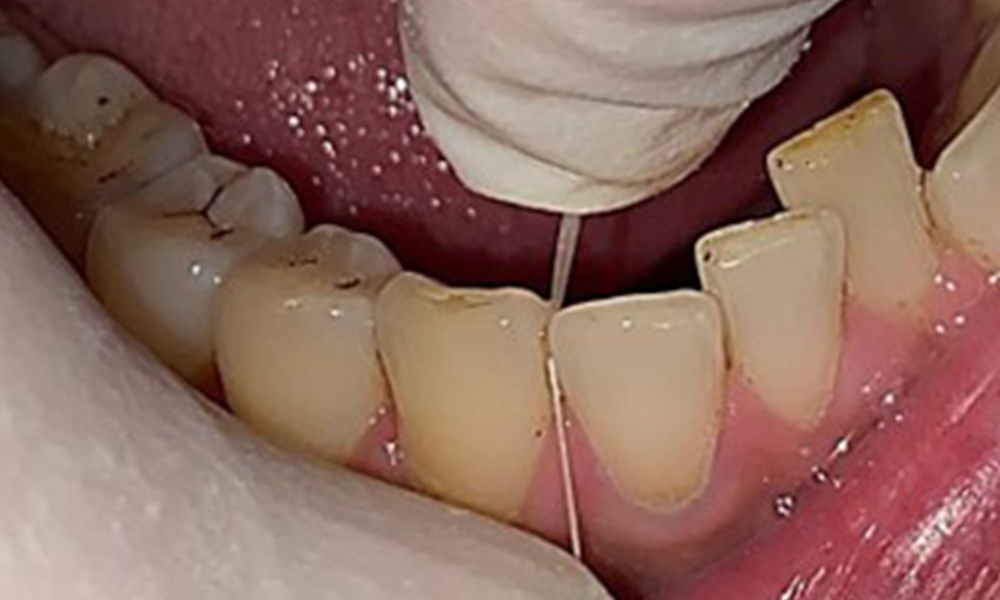

The patient has full dentition with a total of 28 teeth. There were noteworthy erosions and attritions. (Fig. 4, Fig. 5). Due to bruxism, the patient has been wearing a splint with an adjusted bite block at night for many years. The erosions were caused by long-term consumption of isotonic beverages. No periodontal bone loss or active caries were observed.

Instruction and motivation are important components of these appointments. Good home-based intraoral hygiene behaviour and understanding are important for patients. Plaque accumulation is particularly evident in the cervical regions (Fig. 8).

These must be discussed with the patient, and improvements to the teeth-brushing technique must be practised. A soft toothbrush attachment is recommended for home-based intraoral hygiene due to the presence of erosions and attritions.